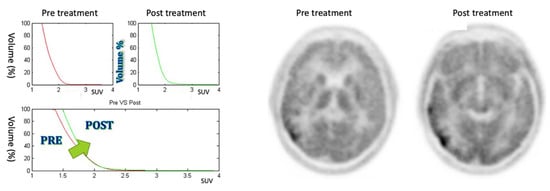

3.3. Negative Response

The patient included in this class shows an increasing AUC and a right shifting of CSH, as it is possible to see in Figure 8 (patient #7). The patient included in this category worsened following therapy.

Figure 8.

On the left: CSH pretreatment (top left); CSH post-treatment (top right); comparison between pre- and post-treatment (bottom) in negative response case: ΔAUC = 8.62%. On the right: PET images of pre- and post-treatment. (For interpretation of the references to colour in this figure legend, the reader is referred to the web version of this article.)